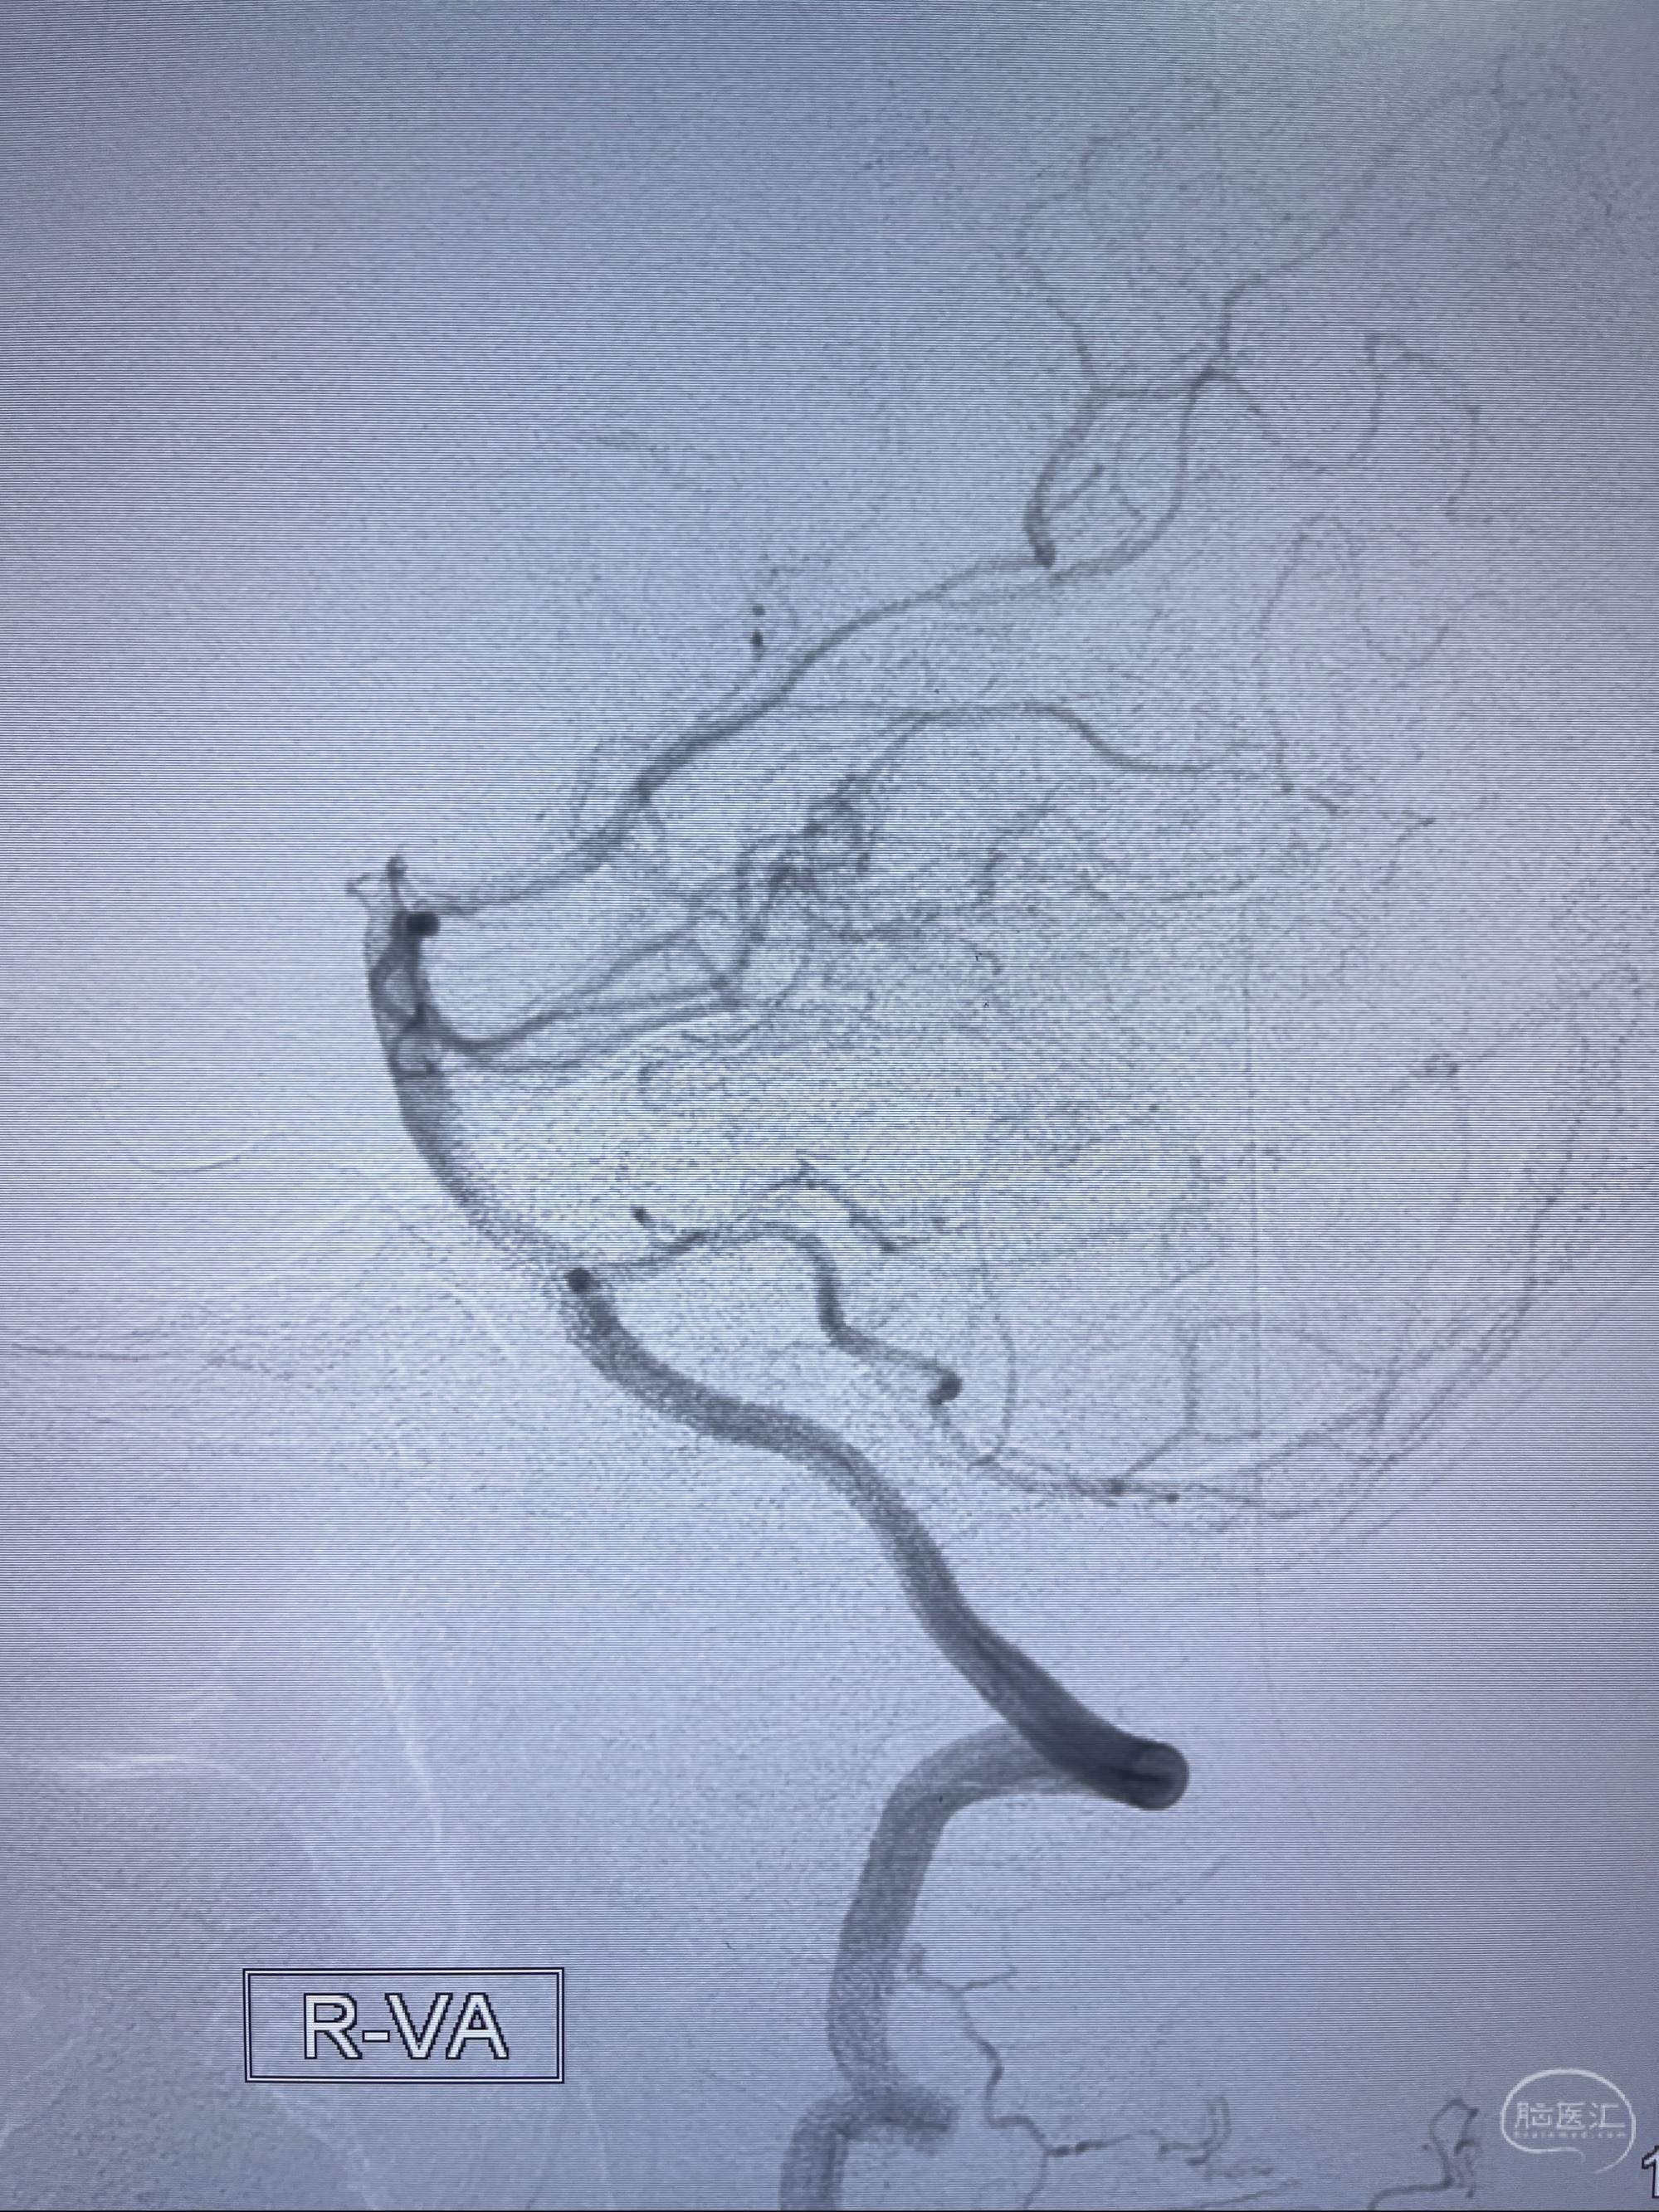

检查;2023-7-18 抚州市第一人民医院 头颈部CTA:左侧大脑前动脉A2段动脉瘤,左侧颈内动脉C4段轻度狭窄,右侧颈内动脉C6段中度狭窄

2023-08-23DSA:左侧前交通动脉瘤,左侧A3/4交界处多发动脉瘤